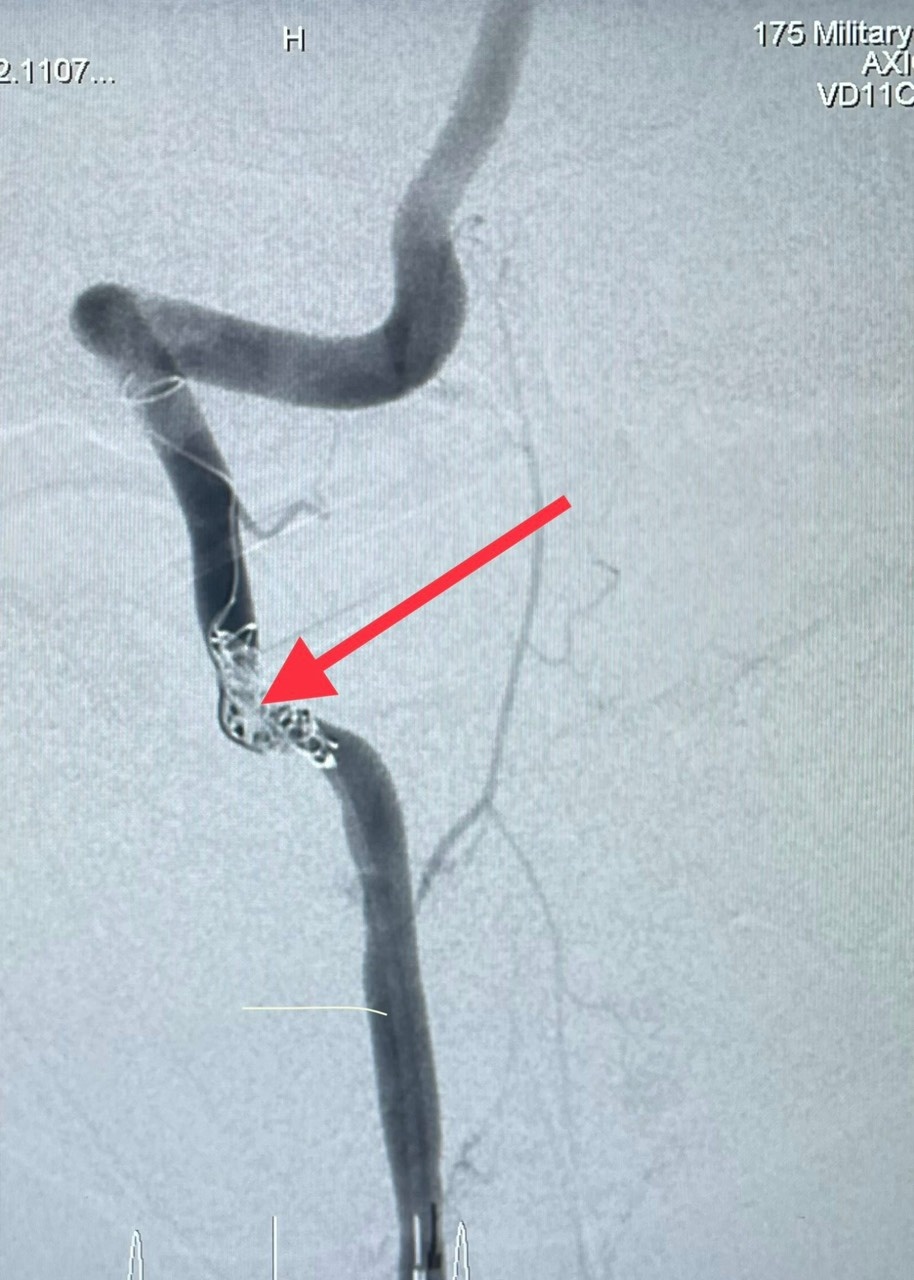

Hình ảnh vết thủng động mạch cổ phải của bệnh nhân. Ảnh: BVCC.

Kết quả cho thấy bệnh nhân bị gãy mỏm ngang đốt sống cổ C2 bên phải, thủng thành bên động mạch đốt sống phải ở vị trí tương ứng. S. nhanh chóng được đặt nội khí quản và đưa lên phòng can thiệp mạch để xử lý chỗ thủng động mạch đốt sống.

Bằng phương pháp can thiệp nội mạch qua da, bác sĩ có thể luồn dụng cụ trong lòng mạch máu đến vị trí động mạch đốt sống bị thủng, xử lý chỗ thủng bằng các vật liệu phù hợp (coil, bóng, keo, stent…).